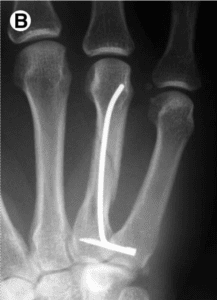

Percutaneous fixation of metacarpal fracture

Article in Operative Techniques in Plastic and Reconstructive Surgery · November 2002 Abstract: Metacarpal shaft fractures are common but consensus on the best mode of treatment has not been established. Open reduction and internal fixation with plates or screws has been performed for severely displaced fractures. Unfortunately, extensor tendon adhesions and/or unsightly scars frequently follow… [Read More]